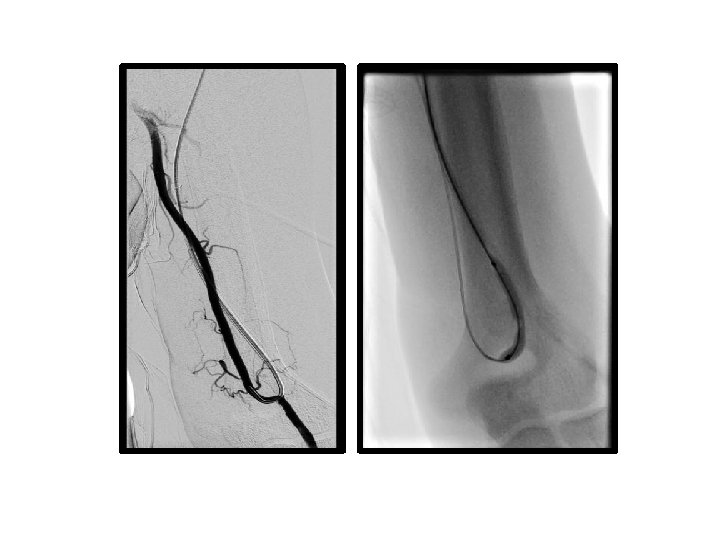

PTA sırasında oluşan venöz komplikasyonlar

• venöz rüptür (%2, 1 - 20) • akut / gecikmiş rüptür • minimal ekstravazasyon ve küçük hematom → damar duvar bütünlüğünde belirgin bozulma ve masif hematom • venöz diseksiyon

venöz rüptür • • • Manuel kompresyon Balon tamponat Stent yerleştirme Embolizasyon Cerrahi ligasyon

venöz rüptür